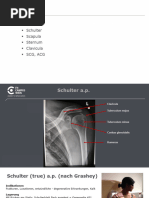

3.

Untersuchung der Schulter